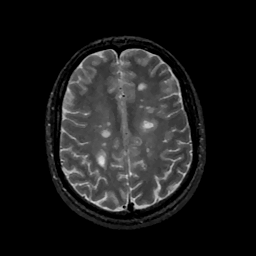

MR Study #11, May 5, 1991 -- Slice #35